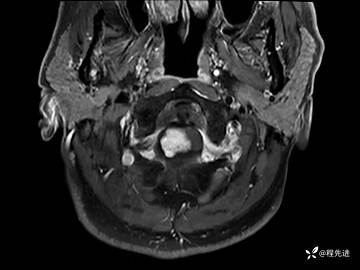

MRI平扫+增强:

T1增强: